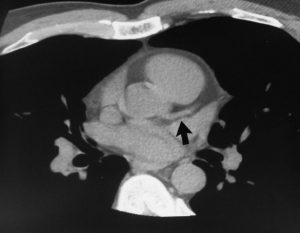

With Heart CT, we can detect and measure the size and density of calcified plaque, presenting that as a quantitative score. The higher the calcium score the greater the amount of underlying CAD and the greater the risk of a subsequent cardiac event.

Severe Calcification